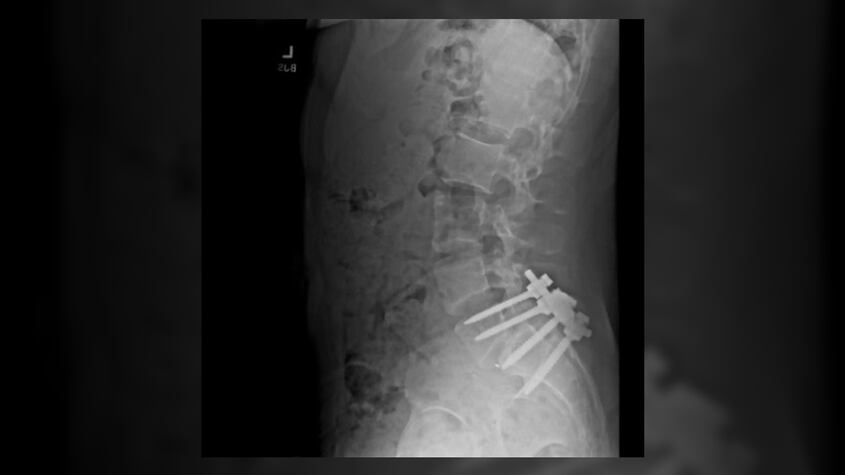

El estudiante universitario esperaba recuperarse durante su estadía en la isla, algo que no ocurrió de inmediato. Luigi Mangione se sometió a una cirugía que solo habría empeorado los dolores que sentía en ese momento. “Se veía atroz, con tornillos gigantes en su columna”, dijo Martin.

Todo indica que aquella cirugía en la espalda fue el detonante que provocó el comportamiento criminal de Luigi Mangione. Aquella radiografía que envió el joven a sus contactos también puede encontrarse en sus redes sociales, señalando la intervención como “un antes y un después” que cerró con el asesinato de Brian Thompson.